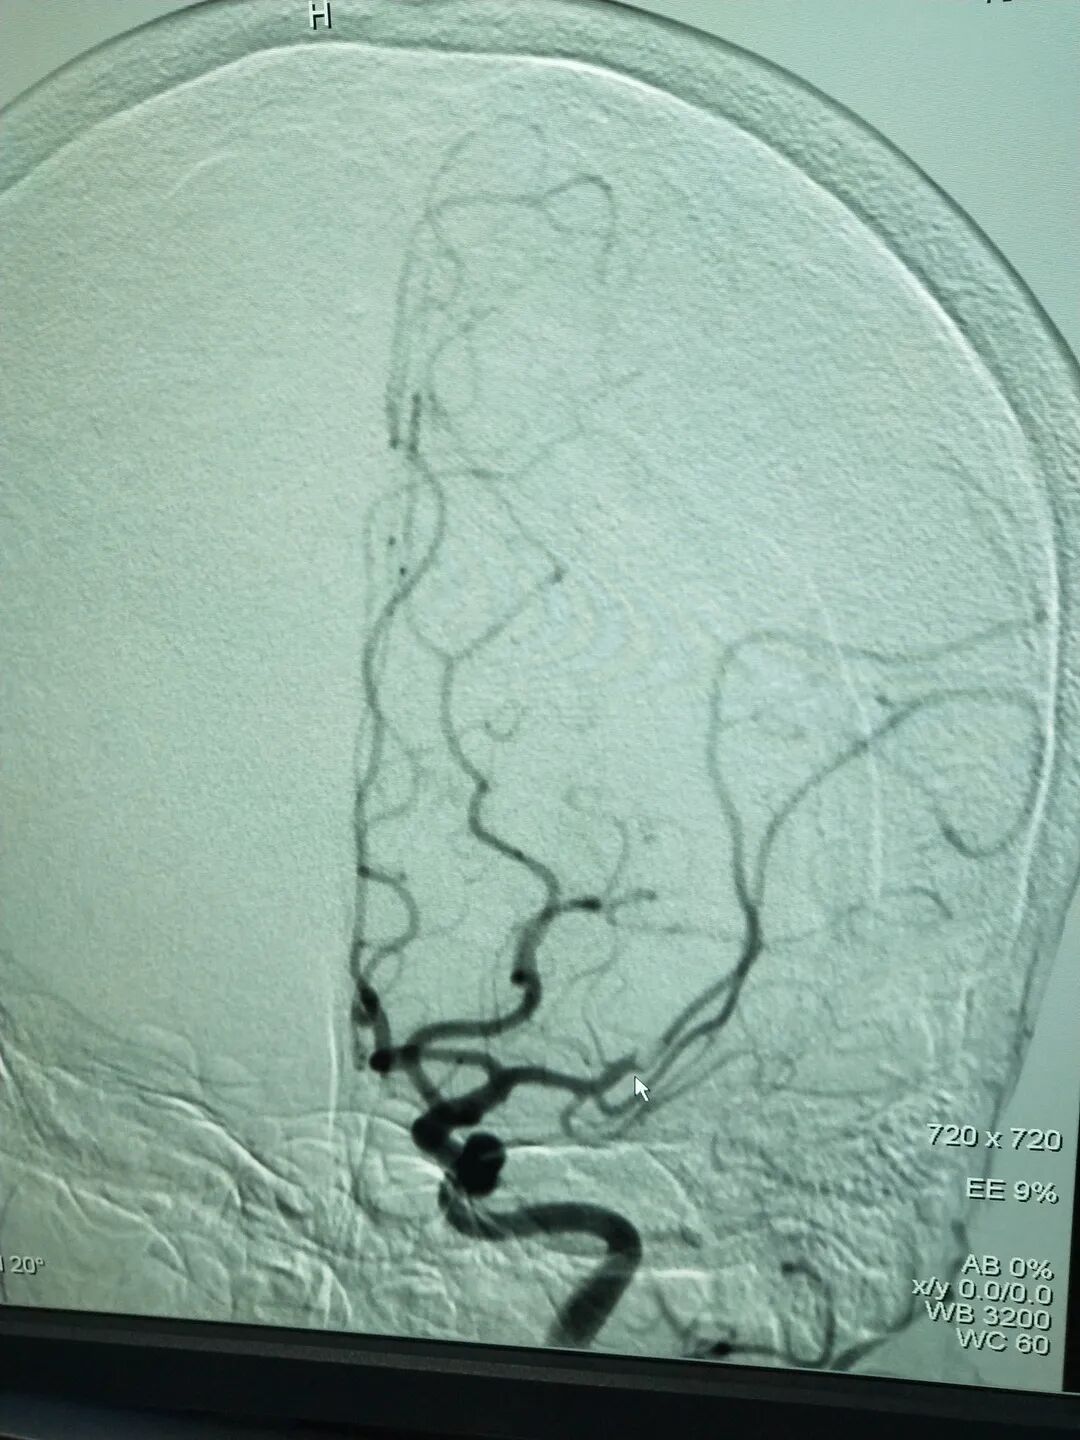

术前血管闭塞